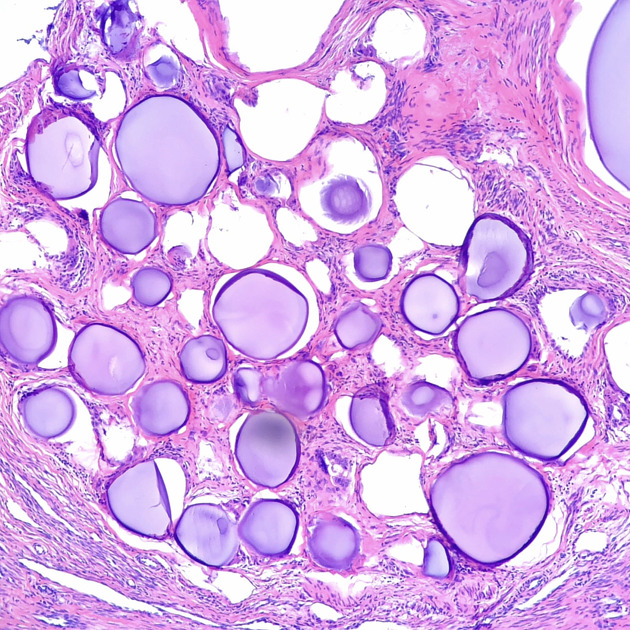

Uterine fibroids are the most common benign neoplasia of reproductive age, creating a substantial burden for millions of women

Uterine fibroid types